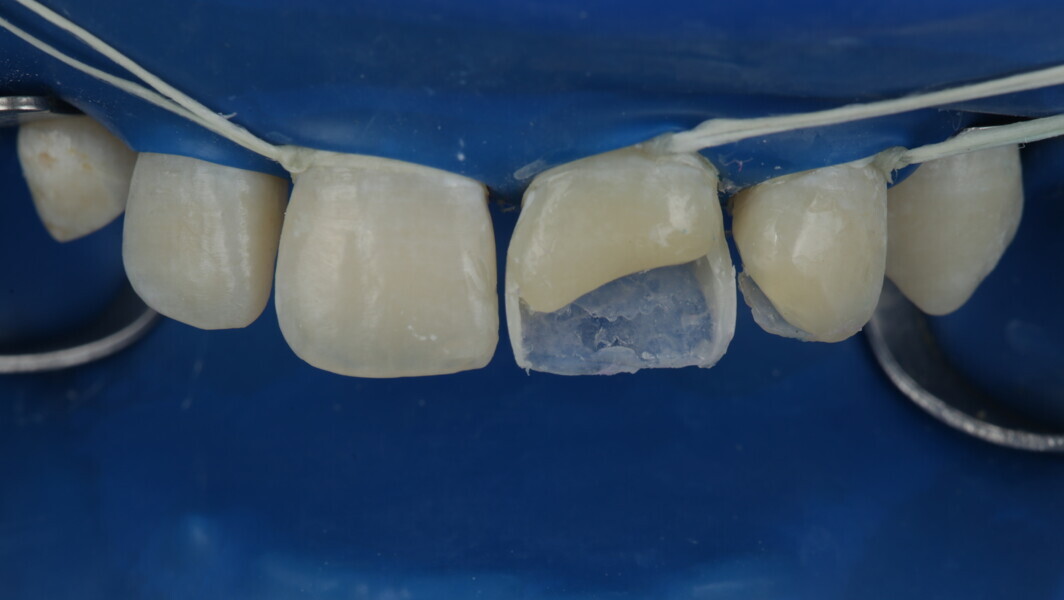

A 10-year-old male patient reported with a complaint of trauma to the upper left central and lateral incisors, involving the enamel and dentin. Direct composite was used in multi-layers and the smile was restored. This article explains detailed steps in the polychromatic layering technique with special emphasis on the finishing and polishing protocol. 3M Espe Filtex Z350 Xt was used with a universal bonding agent.

Fig 19-24: Contact build-up with band and wedge